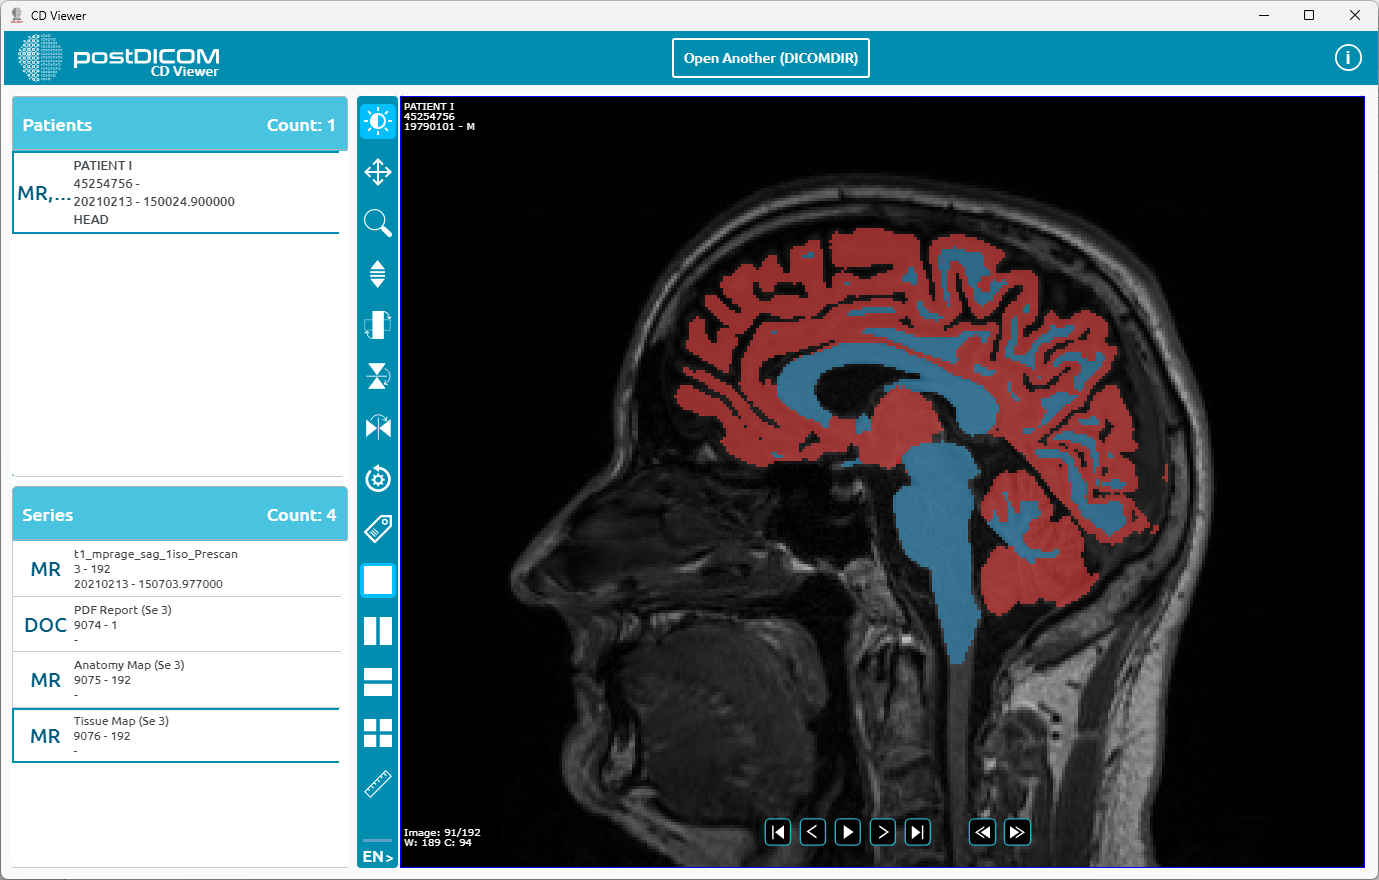

You can start using the application.